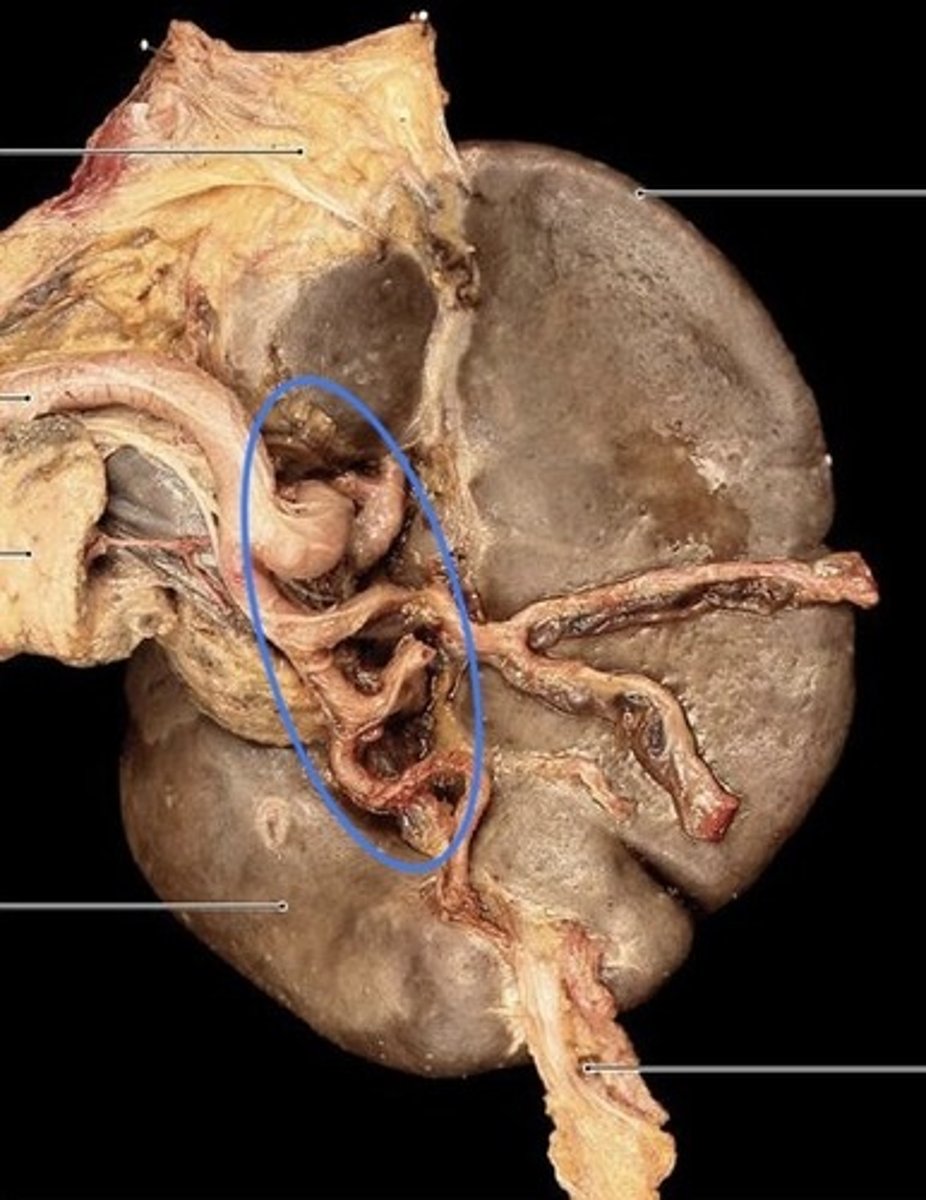

What is this?

Hilum of the spleen

What border is the arrow pointing at?

Sharp anterior border of the spleen

Visceral surface of the spleen